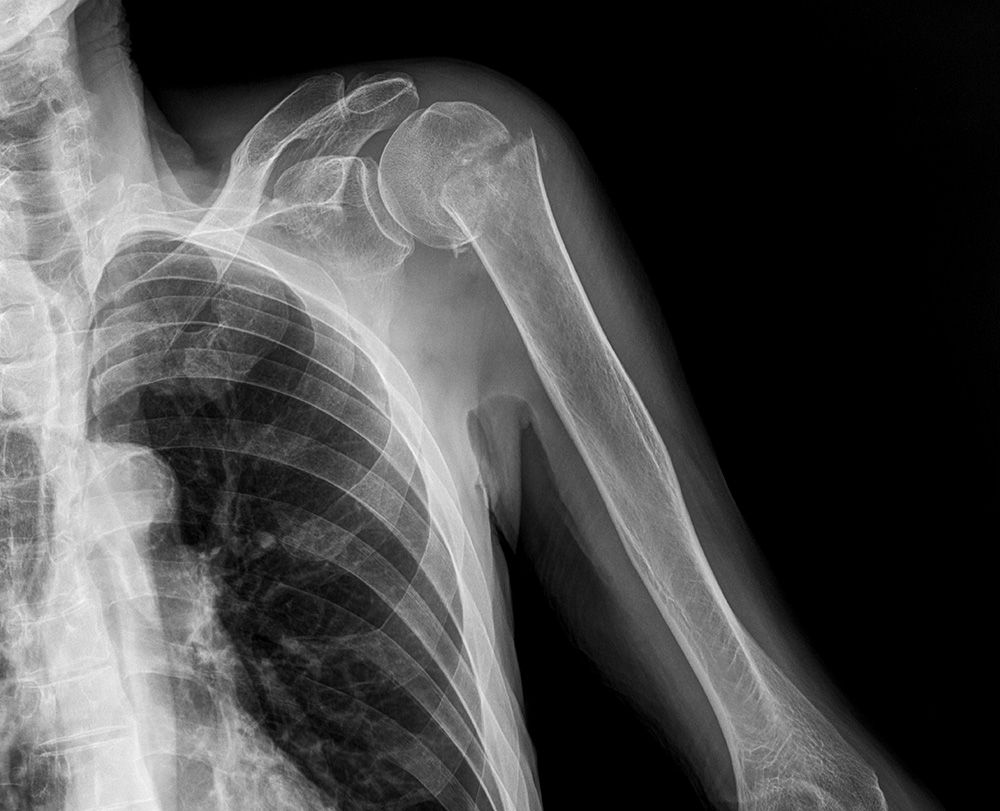

На Р-грамме левого плечевого сустава в 2-х проекциях - межсуставная щель несколько расширена, головка плечевой кости с ровными контурами, смещена несколько кнаруже, имеется перелом в области шейки плечевой кости со смещением костных отломков.